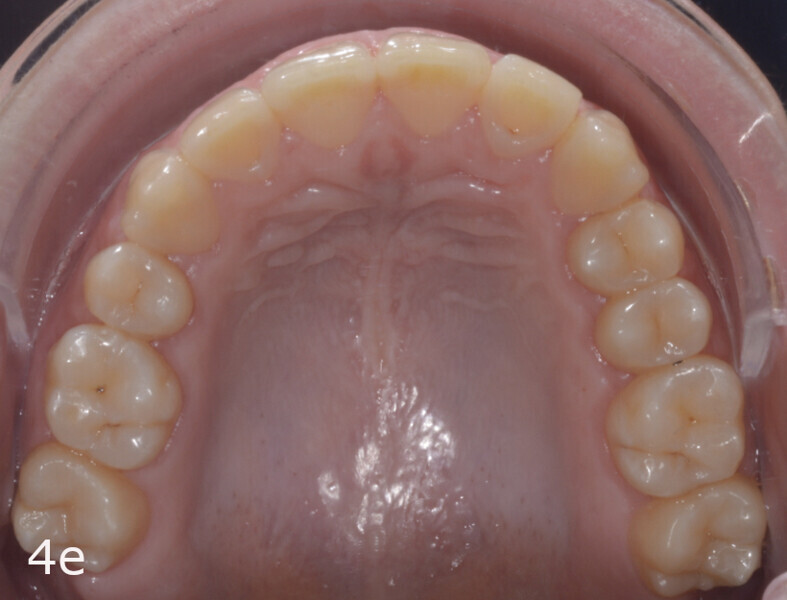

The 23-year-old dolichofacial female patient complained of not being able to chew properly. Facial examination showed a convex profile, an enlarged lower facial height, and a skeletal Class III malocclusion (Figs. 1–3). Intra-oral examination revealed an Angle Class III right subdivision malocclusion, anterior open bite, no overjet and a maxillary dental midline deviated about 3 mm to the right compared with the mandibular dental midline (Fig. 4). The panoramic radiograph confirmed previous extraction of the maxillary right first premolar and the presence of all four third molars (Figs. 5 & 6).

The total treatment time was 15 months. An Angle Class I relationship was established along with adequate anterior and canine guidance, establishing a functional occlusion. This not only ensures optimal masticatory function but also protects the teeth and the temporomandibular joint from excessive force. Maxillary and mandibular fixed retention were installed at the end of the treatment (Figs. 13–19).